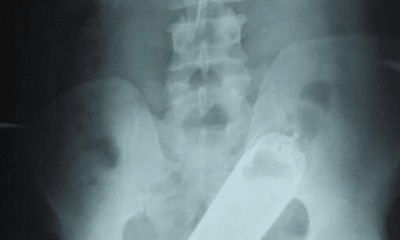

Médicos del Hospital Escuela Universitario de Tegucigalpa extrajeron un frasco de perfume del recto de un paciente que llegó allí con un traumatismo anal y que,...